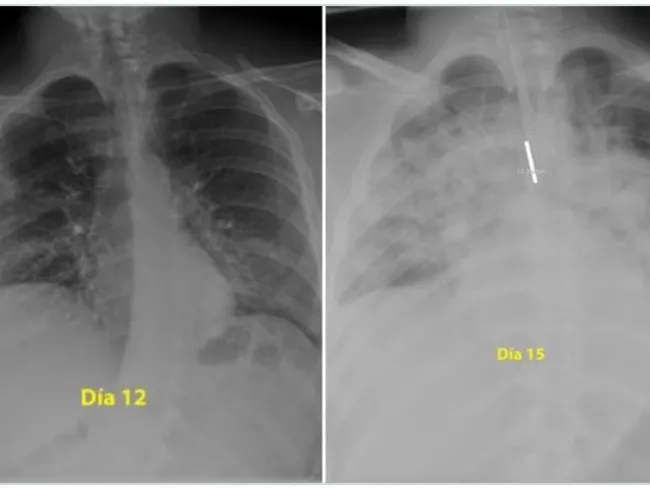

Un medic pneumolog din Spania a postat pe Twitter două radiografii care arată cum s-au degradat, în numai trei zile, plămânii unui tânăr de 28 de ani care a făcut o formă gravă de Covid-19.

Prima fotografie este în a 12-a zi de boală a tânărului, a doua îi înfățișează plămânii în a 15-a zi de boală.

„Pentru cei care cred că sunt nemuritori și continuă să iasă în parc fără să acorde atenție ordinului de a rămâne acasă, acestea sunt radiografiile unui băiat de 28 de ani intubat la Terapie Intensivă în spitalul meu, pentru #coronavirus. Indiciu: plămânii sunt negri, albul este pneumonie”, a scris medicul pe Twitter, potrivit Digi24.